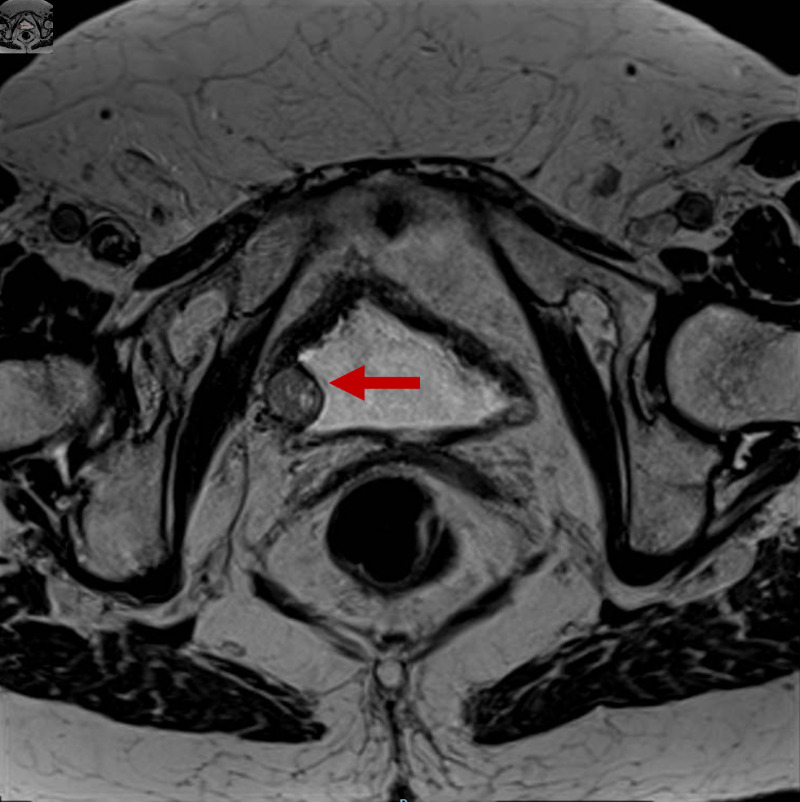

膀胱副神经节瘤占膀胱肿瘤的比例< 0.05%,目前报道的病例很少。由于临床和放射学的发现往往是非特异性的,许多病变被误诊直到手术,使患者暴露于可预防的围手术期儿茶酚胺危机。我们报告一个不寻常的情况下,77岁的妇女,其中17毫米膀胱副神经节瘤偶然发现影像学怀疑克罗恩病。患者完全无症状,儿茶酚胺水平正常。经尿道膀胱切除术(TURB)完全切除,6个月随访未发现复发。本病例说明膀胱副神经节瘤可发生在典型年龄范围之外,且无肾上腺素能症状,强调在鉴别诊断任何界限明确的高血管性膀胱肿块时需要考虑这一实体。早期识别有助于适当的围手术期计划和长期的多学科监测。我们讨论肿瘤的特点,管理和长期监测的重要性。

Bladder paraganglioma accounts for < 0.05% of all bladder tumors, and very few cases have been reported to date. Because clinical and radiological findings are often nonspecific, many lesions are misdiagnosed until surgery, exposing patients to preventable perioperative catecholamine crises. We report an unusual case of a 77-year-old woman, in whom a 17-mm bladder paraganglioma was discovered incidentally during imaging for suspected Crohn's disease. The patient was entirely asymptomatic and had normal catecholamine levels. Transurethral resection of the bladder (TURB) achieved complete excision, and no recurrence was detected at 6-month follow-up. This case illustrates that bladder paraganglioma can occur outside the typical age range and without adrenergic symptoms, emphasizing the need to consider this entity in the differential diagnosis of any well-circumscribed, hypervascular bladder mass. Early recognition enables appropriate perioperative planning and long-term multidisciplinary surveillance. We discuss the tumor's characteristics, management, and the importance of long-term surveillance.